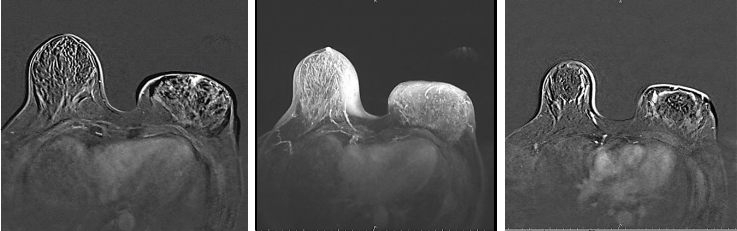

乳腺增强MRI提示左乳皮肤及乳晕增厚,乳头略凹陷,皮下腺体结构紊乱。左乳较右侧明显增大。左乳可见巨大肿块影,大小约12.3cm×6.7cm,T1WI呈等信号,T2WI呈稍高信号,局部DWI呈高信号,ADC减低,增强后明显不均匀强化,时间信号曲线呈平台型。左腋下可见多枚淋巴结影,最大者约2.1cm×1.4cm,BI-RADS 5(图4)。

图4.乳腺增强MRI